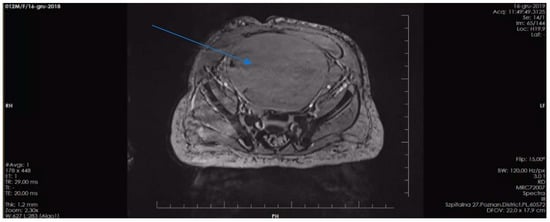

3.3. Pathogenic Variant of the NF1 Gene—Case 2